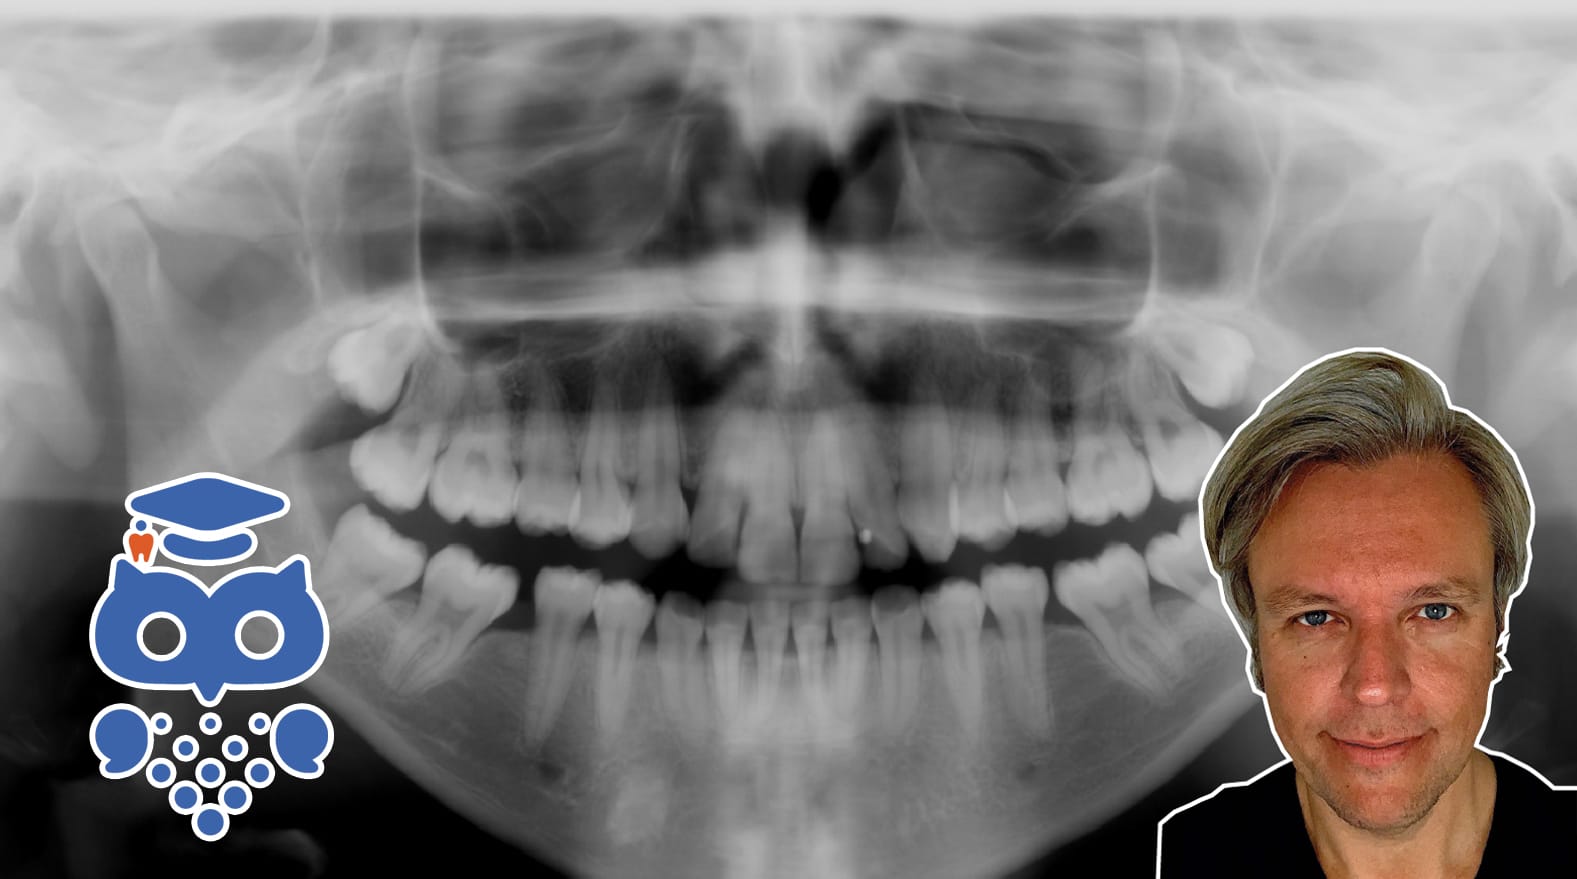

Att tolka röntgenbilder kräver kunskap om anatomi och projektionslära. Tvådimensionella bilder kan ge överlappningar som liknar patologi. Intraorala och panoramaröntgen används inom tandvården, men kräver rätt teknik för att minimera distorsion och förbättra diagnostiken.

De normala anatomiska strukturerna kan ha en variation av olika utseenden och former, vilket gör det viktigt att vara bekant med dessa variationer för att inte felaktigt bedöma normal anatomi som patologi. Ett problem som uppstår vid 2-dimensionell röntgen är att röntgenstrålningens projektion orsakar överlappningar mellan olika anatomiska strukturer, vilket kan imitera en patologisk förändring. Detta skapar en utmaning för oss vid vårt diagnostiska arbete.

Förutom tänderna och det omgivande alveolarbenet finns ett flertal närliggande anatomiska strukturer som avbildas i våra vanligaste dentala röntgenbilder. När vi har kunskap om alla dessa strukturers läge och morfologi, kan vi även förstå hur de kommer att avbildas vid en röntgenundersökning. Därmed kan vi lättare undvika att feltolka informationen i våra röntgenbilder.

PROJEKTIONSGEOMETRI